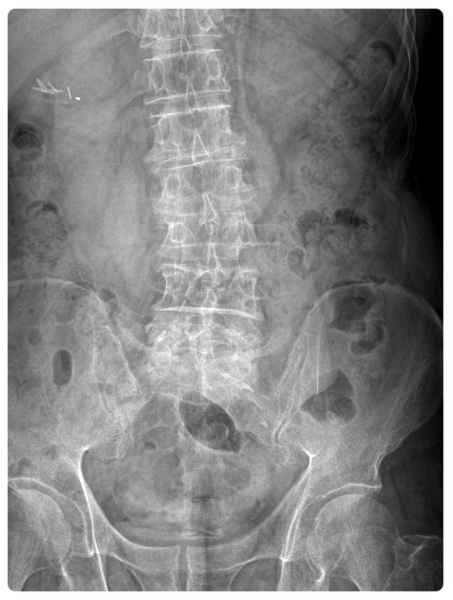

허리디스크(추간판 탈출증)는 척추뼈 사이의 디스크가 밀려나 신경을 압박하면서 생기는 질환입니다.

이 신경이 다리까지 이어져 있기 때문에, 허리 문제도 곧바로 다리 저림으로 나타날 수 있습니다.

특히 초기에는 허리보다 다리에 이상을 먼저 느끼는 경우가 많습니다.

허리 통증이 거의 없더라도, 저림, 감각 둔화, 발끝 당김 같은 증상이 나타난다면 신경 압박 가능성을 의심해 보셔야 합니다.